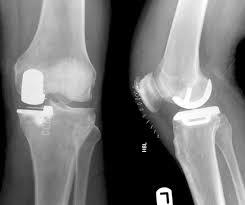

What does this x-ray show?

These are radiographs of an unknown patient taken at an unknown time. They are AP and lateral radiographs of the patient’s left knee. The most pertinent finding is a well-aligned, cemented(?) unicondylar knee replacement in the medial compartment. Surgical clips over the medial aspect of the knee are also visible, suggesting that this radiograph is just a few days post op. There appears to be some osteophytes in the medial aspect of the joint line and some subchondral sclerosis in the lateral compartment, suggestive of OA and potentially explaining the unicondylar prosthesis. There are no fractures visible, peri-prosthetic or otherwise.

TLDR: well-aligned, cemented unicondylar knee replacement of medial compartment with surgical clips visible. Osteophytes and subchondral sclerosis in lateral compartment.